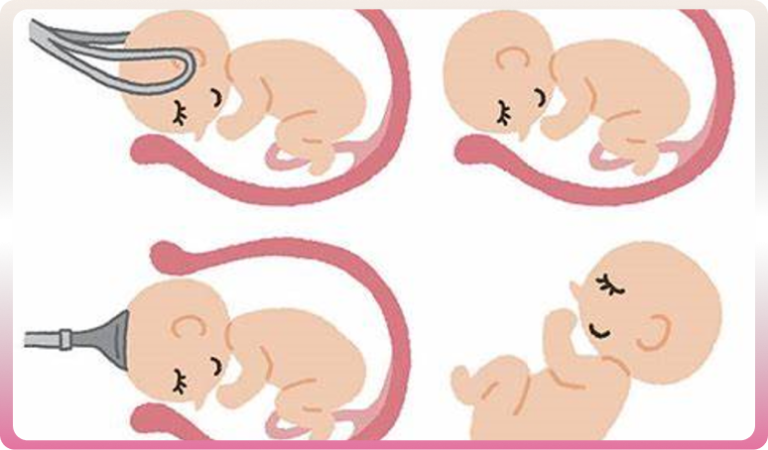

Votre bébé se positionne en vue de l’accouchement en Présentation céphalique habituelle.

Le plus souvent, quelques semaines avant la naissance, le bébé se positionne naturellement pour sa venue au monde : tête en bas et bien fléchie. Cette présentation céphalique permet, le plus souvent, un accouchement normal, par voie basse.

Certains accouchements par voie basse requièrent des techniques instrumentales. On dit que l’accouchement est « assisté ». L’obstétricien peut être amené à les pratiquer lorsque le bébé supporte mal la phase d’expulsion, donne des signes anormaux enregistrés sur le monitoring ou si la maman se fatigue trop, ne peut fournir les efforts nécessaires à l’expulsion. À l’aide de forceps, de spatules ou de ventouses, cette extraction instrumentale est réalisée sous anesthésie locale, péridurale ou générale.

- Le bébé se présente de manière particulière